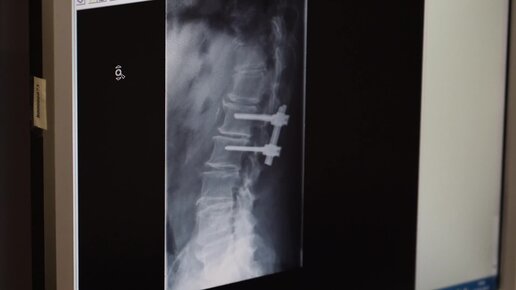

Нейрохирургия ООО "Медсервис"